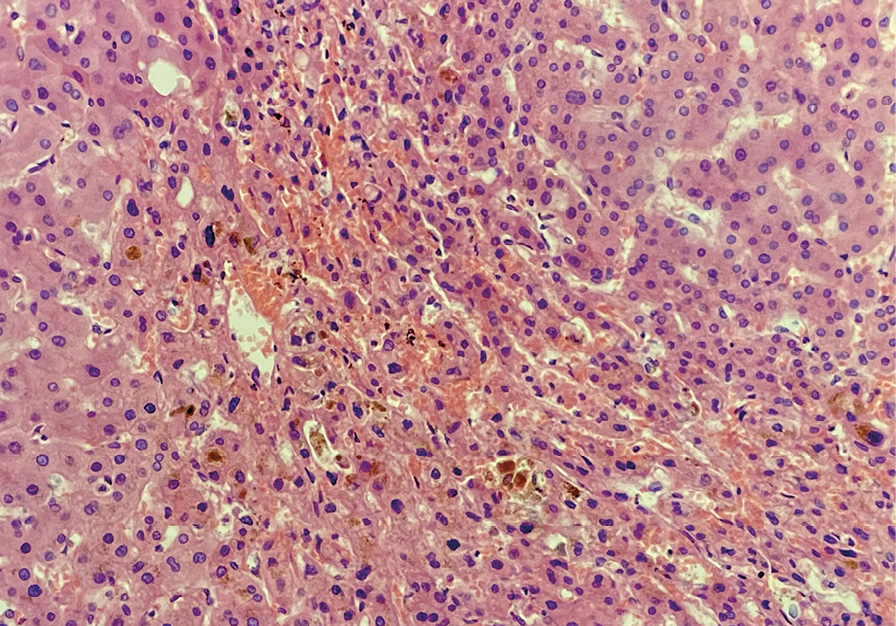

КТ ОГК с контрастированием: КТ-картина интерстициального заболевания легких в стадии формирования «сотового легкого» (рис. 3), малый двусторонний гидроторакс, кардиомегалия. Данных за тромбоэмболию легочной артерии не получено.

Рис. 3. Компьютерная томография органов грудной клетки: аксиальные срезы. Распространенные двусторонние фиброзные изменения на фоне увеличившихся зон «матового стекла», множественные мелкие полостные образования с формированием «сотового легкого», многочисленные бронхоэктазы и бронхиолоэктазы, что соответствует картине возможной обычной интерстициальной пневмонии или фибротическому типу неспецифической интерстициальной пневмонии

На фоне нарастающей полиорганной недостаточности пациентка скончалась. При патоморфологическом исследовании выявлена обычная интерстициальная пневмония с формированием «сотового легкого». Осложнениями стали хроническое легочное сердце, декомпенсация (толщина стенки правого желудочка – 0,8 см, желудочковый индекс – 0,8 (отношение массы правого желудочка к массе левого желудочка в норме 0,4–0,6)), хроническая сердечная недостаточность, двусторонний гидроторакс (по 400 мл в правой и левой плевральных полостях), дистрофия печени, почек, миокарда; признаки портальной гипертензии – спленомегалия (масса 350 г), асцит (1500 мл), гепаторенальный синдром. Данные аутопсии (гистологического исследования) представлены на рис. 4, 5.

Рис. 5. Печень. Явления дуктопении. Пролиферация дуктулярного эпителия. Интраканаликулярный холестаз с образованием желчных пробок. Окраска гематоксилином и эозином; × 400